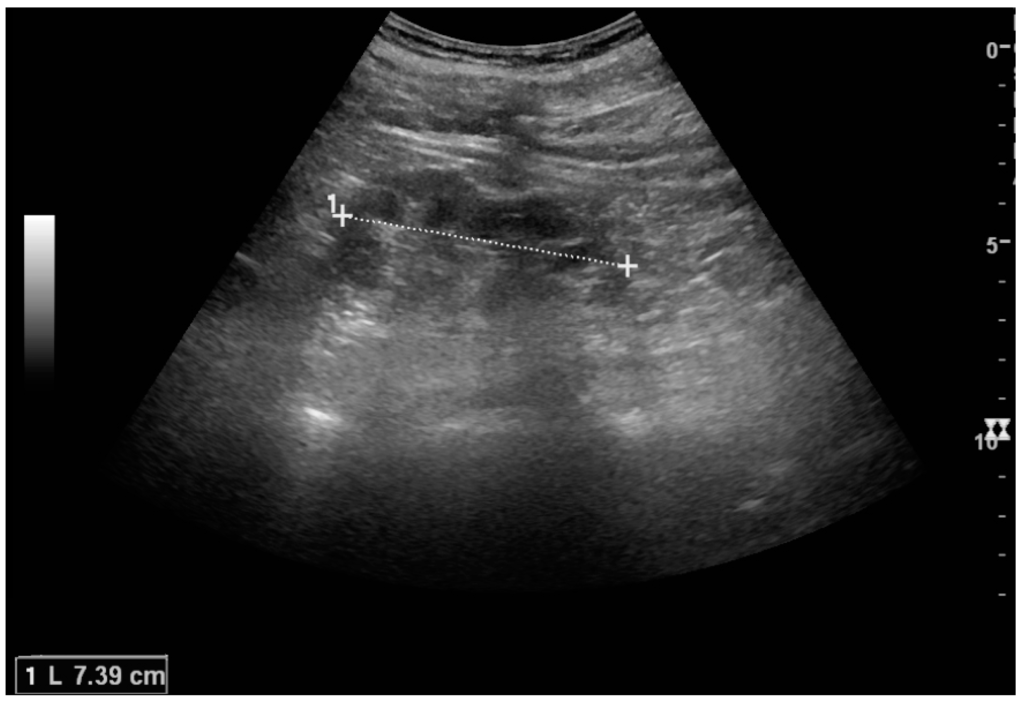

Masses are seen as a distortion of the normal renal architecture. Most renal masses are simple cortical cysts with a round appearance and a smooth thin capsule encompassing anechoic fluid. The incidence increases with age, as at least 50% of people above the age of 50 have a simple cyst in one of the kidneys [12]. Cysts cause posterior enhancement as a consequence of reduced attenuation of the ultrasound within the cyst fluid (Figure 5). The simple cyst is a benign lesion, which does not require further evaluation [13].

Figure 5. Simple cyst with posterior enhancement in an adult kidney. Measurement of kidney length on the US image is illustrated by ‘+’ and a dashed line.